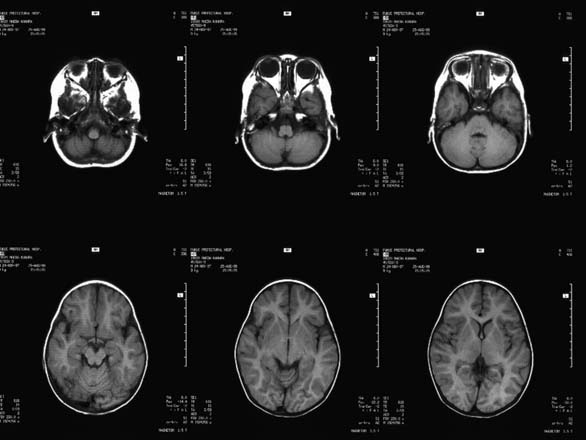

CaseHE02

- Age/Sex: 3 M

- Chief Complaint: けいれん発作重積状態

- Clinical Course:

- Lab. Data:

- Images:

- MR T1 (a)

- MR T1 (b)

- MR T2 (a)

- MR T2 (b)

- Tc-99m ECD Aug/27

- Tc-99m ECD Aug/31